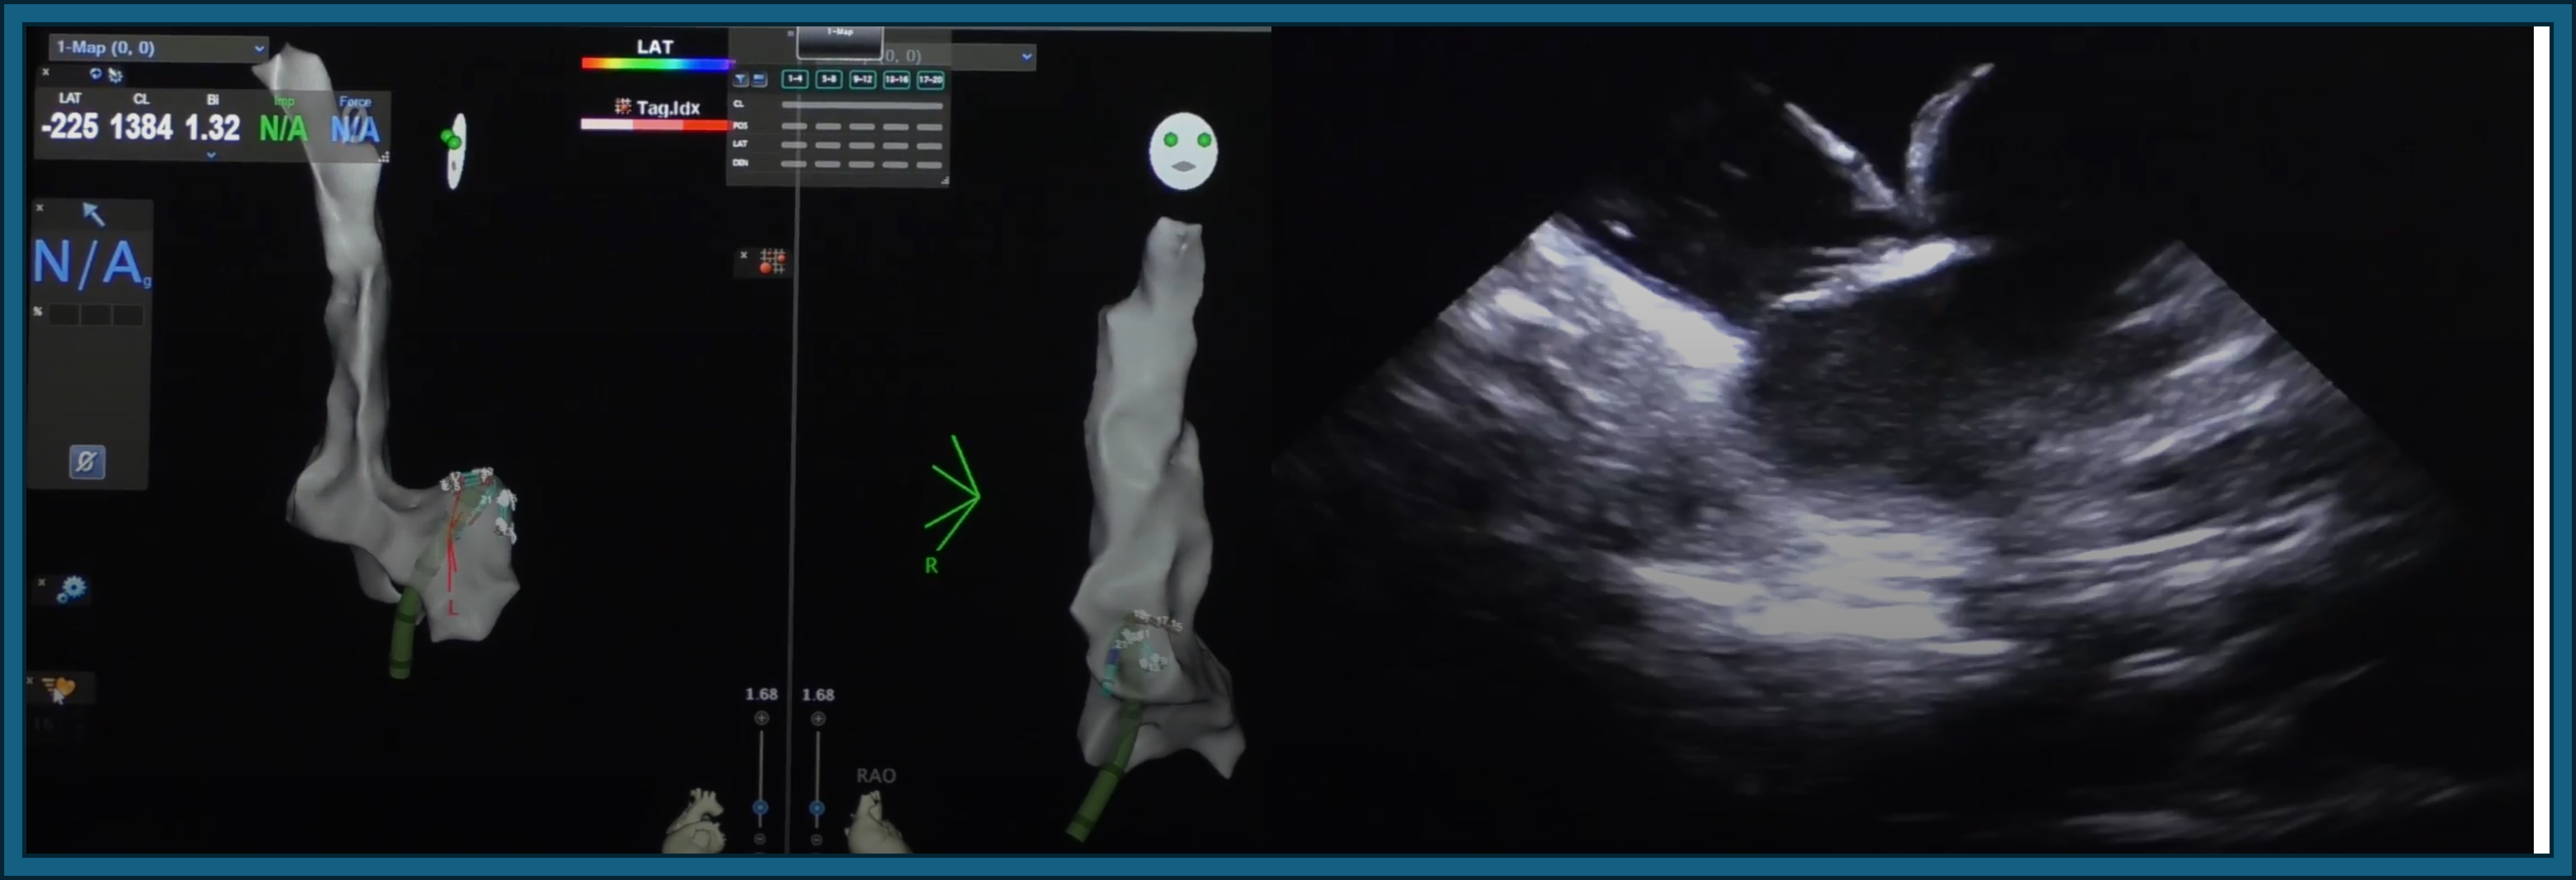

Introducción: Las indicaciones de ablación con sistema tridimensional en pacie...